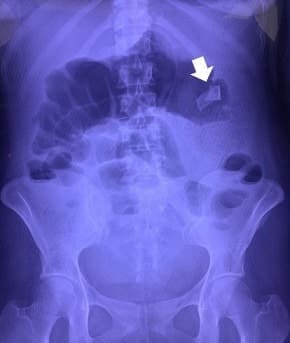

Al examen físico se encontró una masa móvil en el cuadrante superior izquierdo del abdomen. Se realizó radiografía de abdomen donde observan probable cinta radiopaca de textil quirúrgico (figura 1).

Figura 1. Radiografía de abdomen donde se aprecia cinta radiopaca de compresa quirúrgica

(flecha blanca). Fuente: Fotografía propia de los autores.